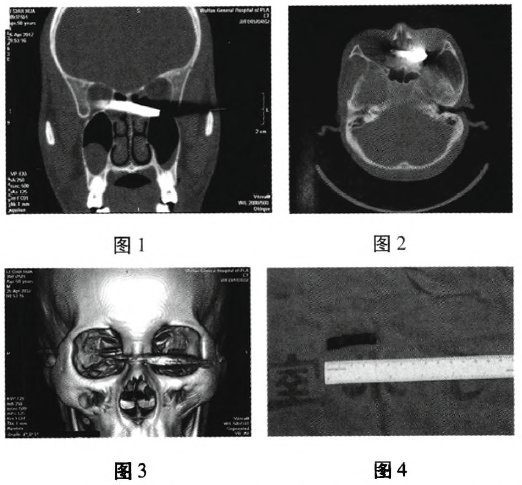

手术过程:全身麻醉。经鼻根部右侧皮肤切开,分离骨膜,注意保护泪囊,咬骨钳去除部分眼眶内下壁、右侧部分鼻根部鼻骨及部分鼻黏膜,暴露筛窦,沿异物纵轴退出异物。见异物大小约40mmx8mm(图4)。3.5%双氧水、碘伏原液以及生理盐水冲洗手术区,观察无异物残留,鼻腔碘纺纱条填塞,分层缝合。并行外侧结膜下探察,外直肌无损伤,予清创缝合,术后给予抗生素抗炎、预防破伤风等治疗,并针对视网膜挫伤进行相应治疗。术后7d拆线。术后半月右眼视力:0.1,眼球形态良好,眼球运动正常,复查CT:眼眶至筛窦内未见高密度影(图5)。